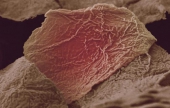

Levenhuk 870T — надежный тринокулярный биологический микроскоп, с помощью которого производится весь спектр наблюдений как в светлом, так и в темном поле. Широко используется в медучреждениях разного типа для урологических, дерматологических, биологических, биохимических, патологоанатомических, цитологических, гематологических и общеклинических лабораторных исследований. А поскольку это тринокуляр, то в комплекте с камерой-окуляром его можно без проблем использовать в качестве цифрового микроскопа. Цена: 650 000 тг. |